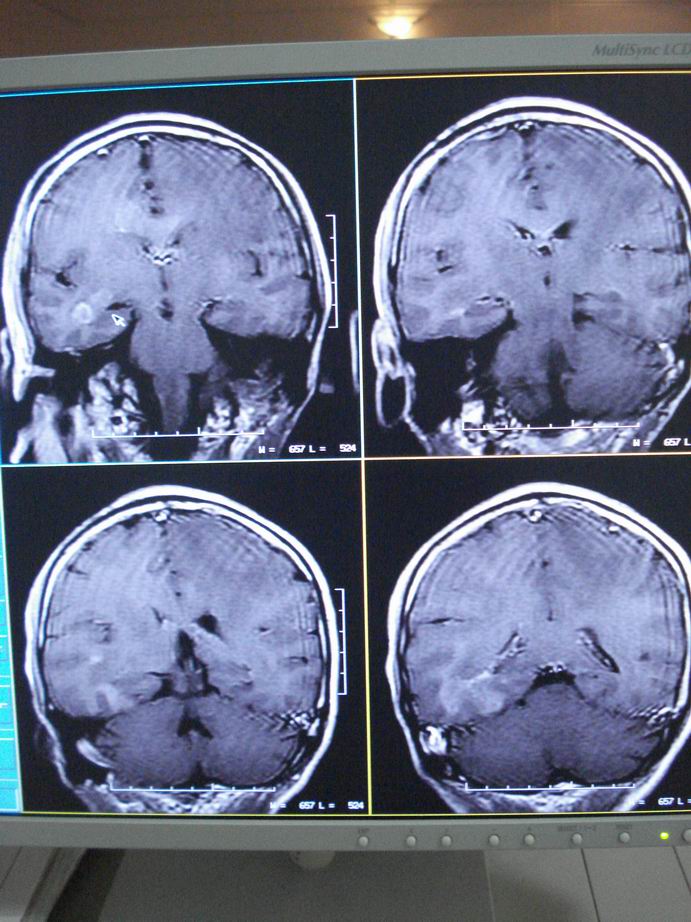

男60岁,左侧肢体乏力及精神异常10天,血压正常,血常规,肝肾功正常,腰穿无异常,请教颅内多发病灶,考虑什么?感染?肿瘤(转移性?)还是其它?

考虑为颅内多发转移瘤

脑内多发性转移瘤。

脑内多发性转移瘤。支持!